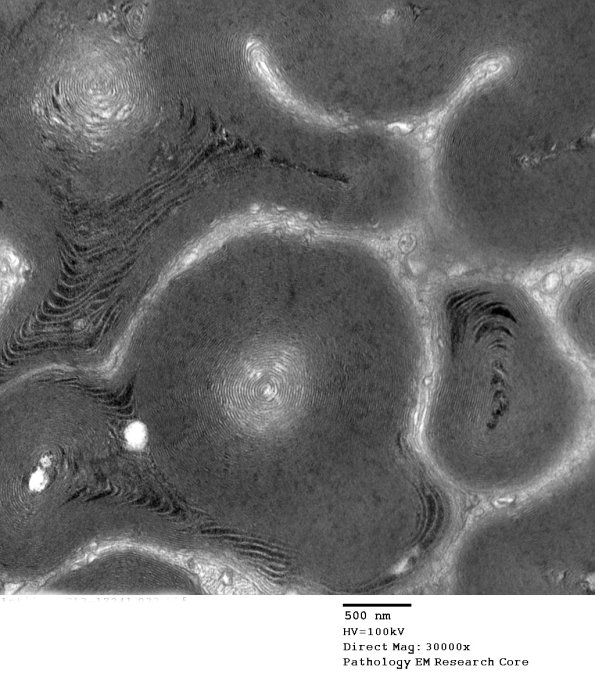

Washington University Experience | PERIPHERAL NEUROPATHY | 0 PNS ARTIFACTS | 13A3 Artifact EM_033 - Copy

Additional image of the artifact. (electron micrograph)